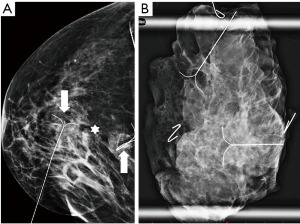

Digital breast tomosynthesis (DBT) is a novel approach in mammography that has the potential to overcome the limits of conventional mammography. It acquires several low-dose images of the breast, and reconstructs a synthetic 2D image with enhanced parenchymal distortion features and multiple slabs/slices of the breast, to enable exploration of 3D anatomy of the breast tissue (Figure 3). DBT detects approx. 15–30% more cancers, which would otherwise be hidden in the breast parenchyma in conventional mammography, and also helps to reduce the false positivity caused by superposition of normal structures mimicking pathology by 15–20% (23). Although very promising, DBT is still used mainly within clinical trials and its broader use as a screening method is still not routinely adopted. In comparison with mammography, DBT requires longer reading time, the radiation dose can be slightly higher and achievement of the main goal—reduction of interval cancers—has not yet been confidently demonstrated (24).

Figure 10 Mammography of the left breast in cranio-caudal view (A) with architectural distortion (arrow). The distortion is more visible in DBT (B) (arrow). Ultrasound (C) reveals subtle finding of irregular area of decreased echogenicity (arrow). MRI (D) shows extensive area of non-mass-like enhancement in the whole lateral part of the breast (arrow). DBT, digital breast tomosynthesis; MRI, magnetic resonance imaging. - Diagnostic assessment, a patient of 45 years of age with a palpable lump on the right side for 2 months. In mammography with higher proportion of fibroglandular tissue (category C) several areas of increased density with irregular margins and architectural distortions are visible. Ultrasound confirms more than one lesion. MRI demonstrates a large area of enhancement up to 7 cm (Figure 11).